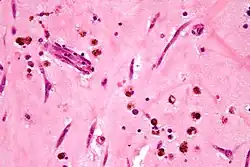

| Micrograph of an atrial myxoma. H&E stain. | |

A myxoma (New Latin from Greek muxa 'mucus') is a myxoid tumor of primitive connective tissue.[1] It is most commonly found in the heart (and is the most common primary tumor of the heart in adults) but can also occur in other locations.